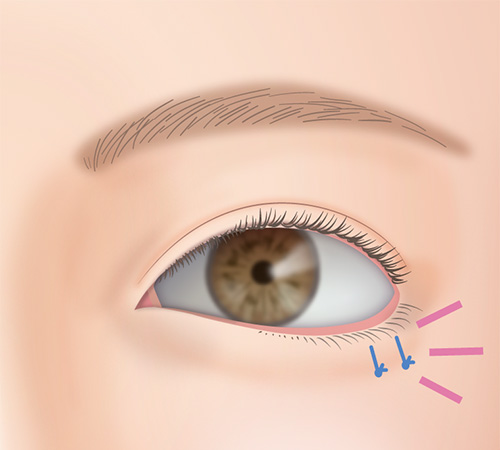

主に下まぶたのたるみ取りなどで皮膚を取りすぎると、常に粘膜が見えている状態になる場合があります。

改善を望むのであればとりすぎてしまった下まぶたを皮膚移植によって修正することが可能です。

ただし、機能の回復と引き換えに傷跡がかなり目立つ可能性があります。